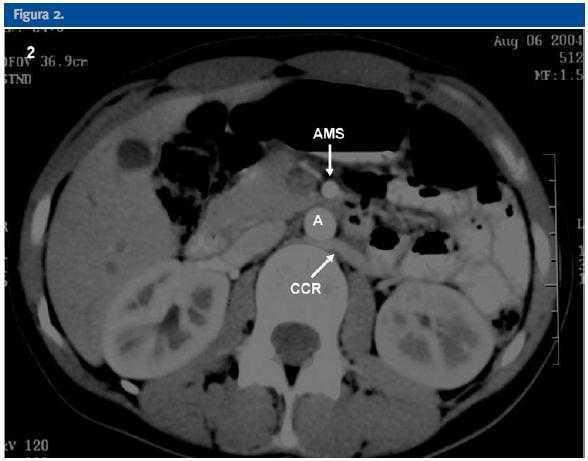

Mujer de 29 años de edad remitida desde Atención Primaria para estudio de microhematuria. Presentaba antecedentes de asma bronquial en tratamiento con inhaladores. A la exploración física se evidenciaba presión arterial normal y hábito asténico (Peso: 47 Kg; Talla: 162 cm; IMC: 17,9 Kg/m2). La enferma refería clínica de larga evolución consistente en astenia y dolor recidivante en flanco izquierdo que se intensificaba durante el ejercicio físico. A lo largo de su seguimiento presentó dos episodios de hematuria macroscópica de 4 y 10 días de evolución sin relación con cuadros infecciosos. En las pruebas complementarias iniciales presentaba función renal normal con proteinuria de 0,3 g/d y sedimento con microhematuria mantenida (15-20 hematíes por campo) aunque sin hematíes dismórficos. Las eliminaciones urinarias de calcio, fósforo, ácido úrico, oxálico y magnesio fueron normales. La citología urinaria para células malignas fue negativa. En el estudio inmunológico no se apreció ningún dato anormal (Tabla 1). La ecografía abdominal y la urografía intravenosa no revelaron ninguna alteración de interés. Ante la normalidad de estas pruebas radiológicas se realizó ecografía Doppler color renal y tomografía computarizada (TC) (figs 1,2 y 3).

La ecografía Doppler, al igual que la TC realizada, demostró la compresión de la vena renal izquierda entre la arteria mesentérica superior (AMS) y la aorta abdominal (A). En la ecografía Doppler se demostraba un efecto de pinza sobre la vena renal principal izquierda (VRI) que se traducía en una asimetría de flujo venoso entre ambos riñones, siendo de amplitud y pulsatibilidad disminuída en el lado izquierdo. Se observaba también circulación colateral retroaórtica (CCR) con inversión de flujo en la vena ovárica izquierda. En la TC se evidenciaba circulación colateral retroaórtica (vena renal retroaórtica accesoria).

Figura 2.